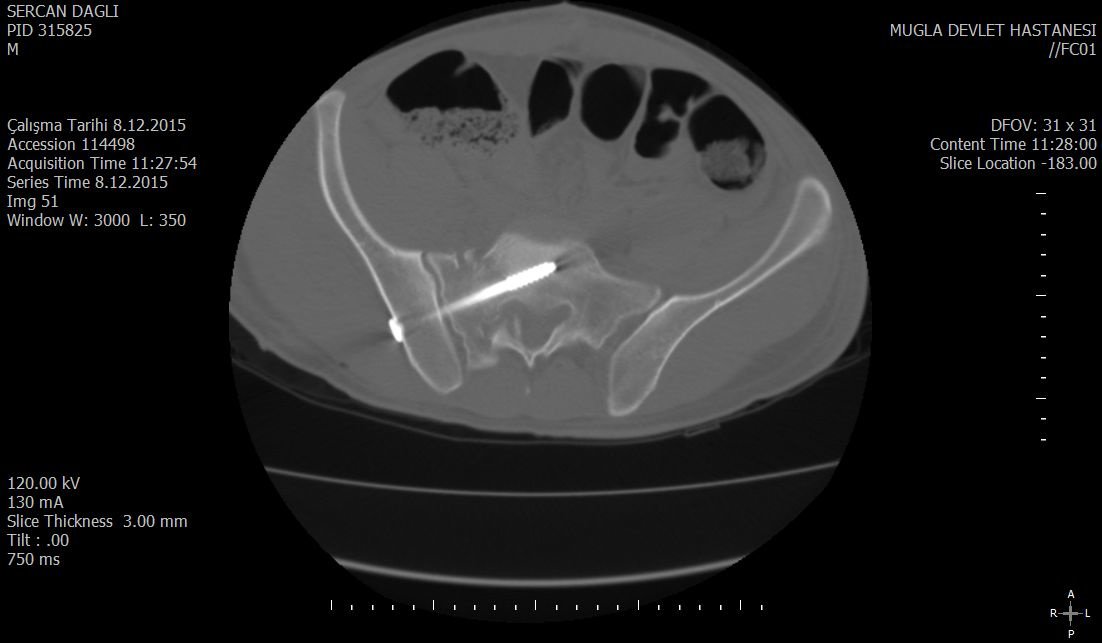

حول كاريا جراحة العظام وإعادة التأهيل عيادة كاريا جراحة العظام وإعادة التأهيل في موغلا ، تركيا تقدم رعاية العظام عالية الجودة ، بما في ذلك العلاجات الجراحية وغير الجراحية من قبل Assoc. البروفيسور الدكتور جيم يالين KILIN وفريقه. وهم متخصصون في الصدمات والإصابات الرياضية وجراحات تقويم المفاصل ، ولديهم خبرة في العلاج الطبيعي لإعادة التأهيل.